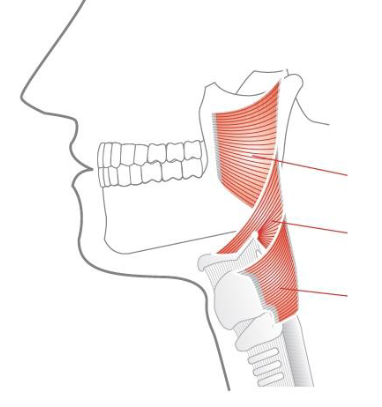

7

Q

what actions does the ant and post parts of the temporalis do

A

ant= elevate mandible

post = retract mandible

10

what are the 3 muscles

what innerevates them

pharyngeal constrictors